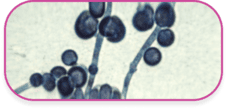

Основные возбудители кандидоза у человека

грибы рода Candida

В состав рода Candida входит около 150 видов грибов, 20 из которых могут вызывать заболевания у человека2